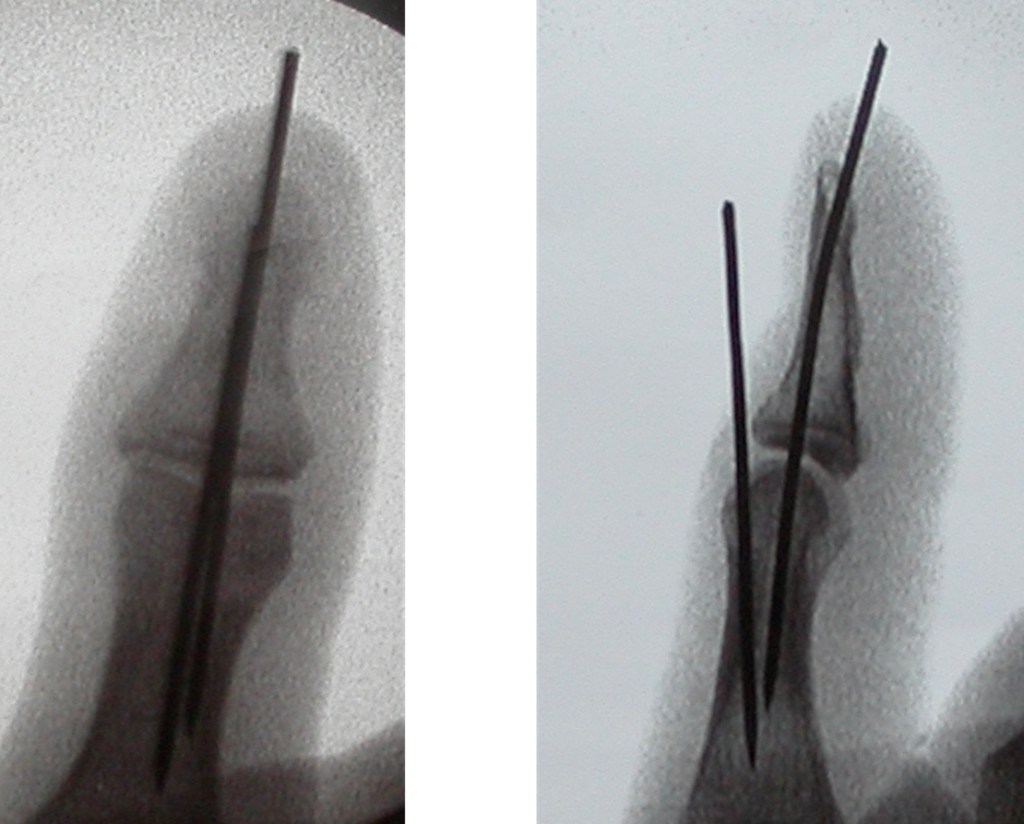

An UNSTABLE mallet injury is usually treated with an operation, and wires used to fix the bone in position. This may also be necessary if the injury is associated with a deep cut. The wires are removed at around 6 weeks, and by this stage, the bone has healed and the injury now stable. The rest of the hand can mobilise normally during the first 6 weeks, and the injured joint mobilised immediately following removal of the wires.